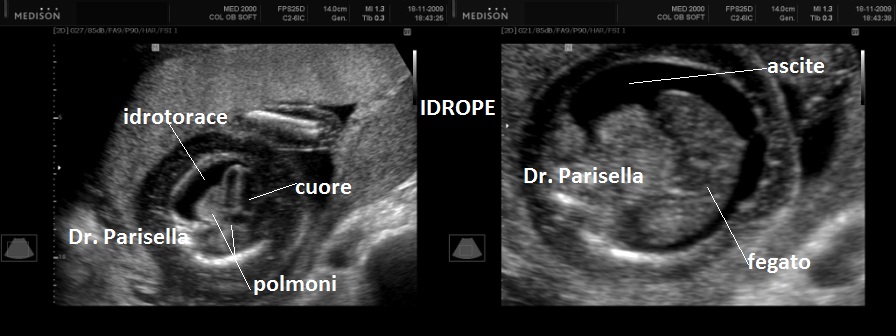

La forma grave (perinatale, infantile) è simile all'osteogenesi imperfetta tipo II con severo accorciamento degli arti (specie femore ed omero) la cui diafisi appare ricurva, ipoplasia toracica grave, ipomineralizzazione diffusa ad eccezione delle clavicole, idrope (nelle forme ad insorgenza precoce), polidramnios; incostantemente si hanno coste sottili e sedi di fratture.

MICROMELIA SEVERA, IPOPLASIA TORACICA SEVERA, IPOMINERALIZZAZIONE ESTREMA TRANNE LE CLAVICOLE, IDROPE (evidente principalmente nei casi a riscontro precoce), DEFORMAZIONE DELLA VOLTA CRANICA ALLA COMPRESSIONE IMPRESSA DALLA SONDA.